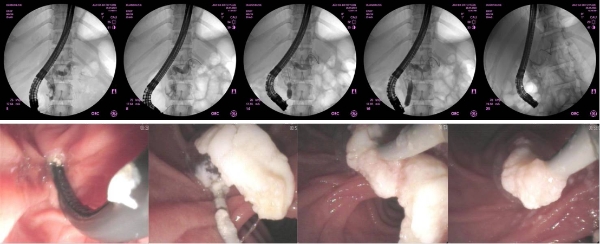

胰管镜探查于胰管内可见广泛结石形成

ERCP下从胰管内取出大量结石